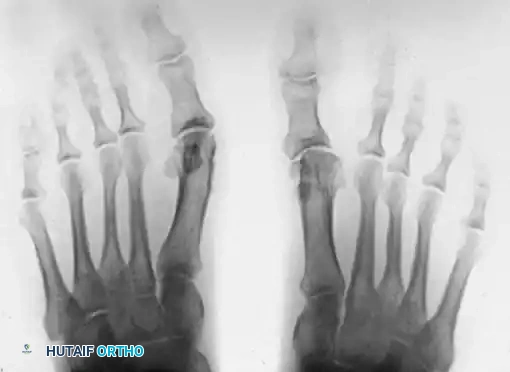

Figure 81-77: (A) Fixed hallux varus after a McBride bunionectomy. (B) Hallux varus after a McBride bunionectomy with fibular sesamoid excision. Removing the fibular sesamoid eliminates the valgus-producing moments of the adductor hallucis and the lateral head of the flexor hallucis brevis.

Figure 81-76: (A) Relatively mild hallux varus with symptomatic degenerative arthritis of the first metatarsophalangeal joint. (B and C) Arthrodesis was chosen as the definitive treatment due to the presence of advanced degenerative joint disease.

Figure 81-79: (A) Preoperative hallux valgus deformity. (B) Postoperative dislocation of the tibial sesamoid following a distal metatarsal osteotomy combined with a fibular sesamoidectomy, leading to profound muscle imbalance.